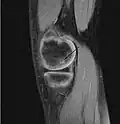

A large flap lesion in the femur head typical of late stage Osteochondritis dissecans. In this case, the lesion was caused by avascular necrosis of the bone just under the cartilage.

Magnetic resonance imaging (MRI) is useful for staging OCD lesions, evaluating the integrity of the joint surface, and distinguishing normal variants of bone formation from OCD by showing bone and cartilage edema in the area of the irregularity. MRI provides information regarding features of the articular cartilage and bone under the cartilage, including edema, fractures, fluid interfaces, articular surface integrity, and fragment displacement.[37][38] A low T1 and high T2 signal at the fragment interface is seen in active lesions. This indicates an unstable lesion or recent microfractures.[30] While MRI and arthroscopy have a close correlation, X-ray films tend to be less inductive of similar MRI results.[38]